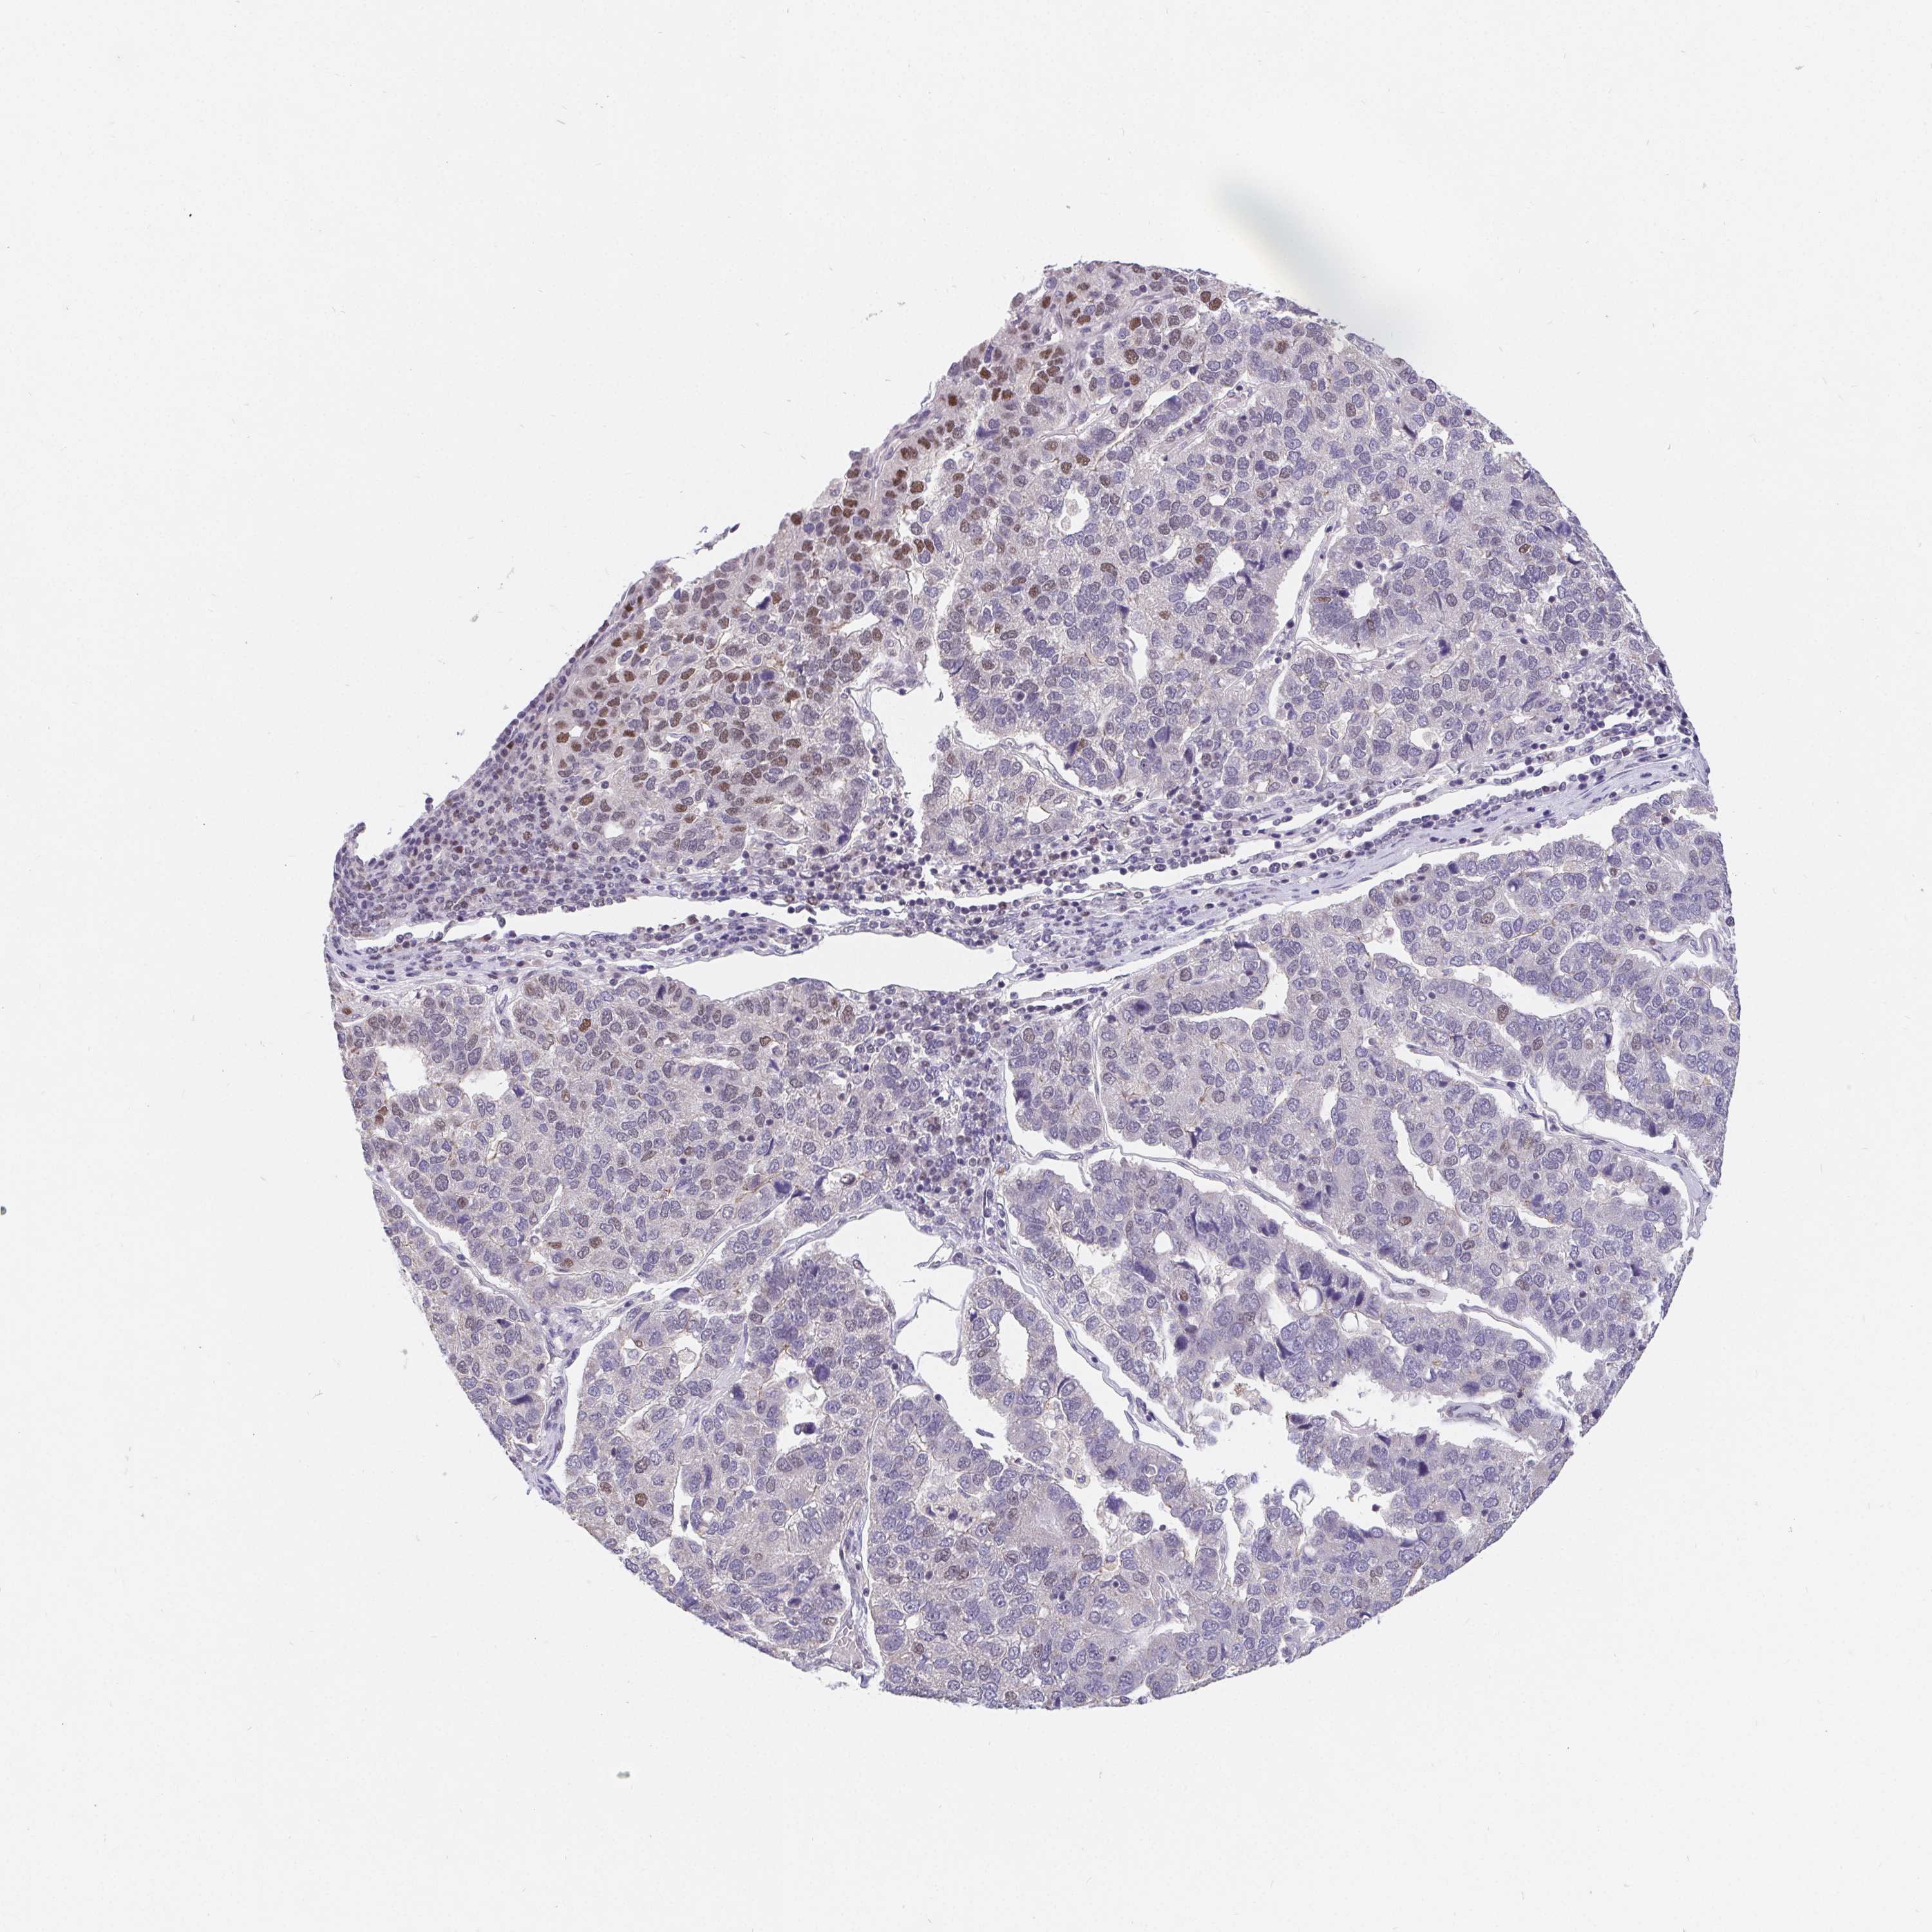

PANCREATIC CANCER - Protein expressioni

A mouse-over function shows sample information and annotation data. Click on an image to view it in a full screen mode. Samples can be filtered based on level of antibody staining by selecting one or several of the following categories: high, medium, low and not detected. The assay and annotation is described here.

Note that samples used for immunohistochemistry by the Human Protein Atlas do not correspond to samples in the TCGA dataset.

Antibody stainingi

Antibody staining in the annotated cell types in the current human tissue is reported as not detected, low, medium, or high, based on conventional immunohistochemistry profiling in selected tissues. This score is based on the combination of the staining intensity and fraction of stained cells.

Each image is clickable and will lead to virtual microscopy that enables deeper exploration of all samples and also displays staining intensity scores, fraction scores and subcellular localization as well as patient and tissue information for each sample.

Antibody HPA064323

Antibody CAB002608

Staining

High

Medium

Low

Not detected

Intensity

Strong

Moderate

Weak

Negative

Quantity

>75%

75%-25%

<25%

None

Location

Nuclear

Cytoplasmic/membranous

Cytoplasmic/membranous,nuclear

Adenocarcinoma, NOS